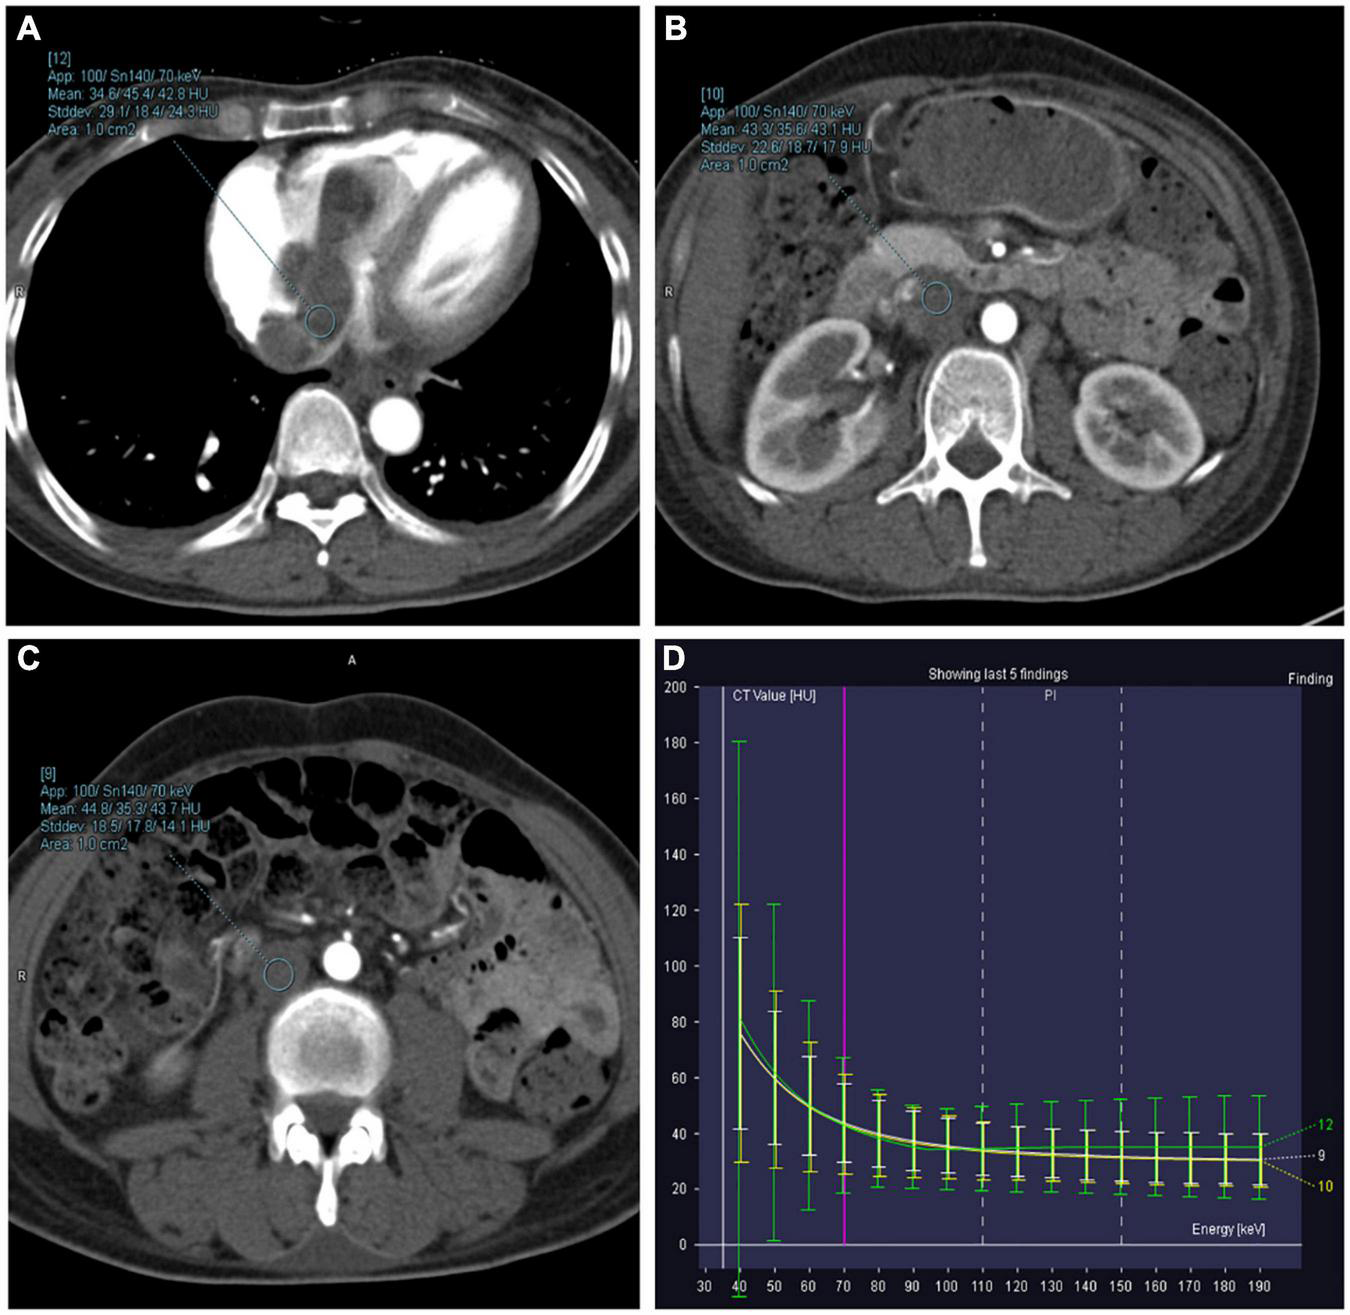

FIGURE 4

Axial dual-energy computed tomography (CT) images show tortuous and enlarged paracervical veins. (A–G) 40–100 keV VMIs (10-keV interval). (H) Iodine density map. (I) Z effective map.

The objective quantitative SNR and CNR values are displayed in Table 2. VMI, at 40 keV, exhibited the highest SNR and CNR (SNR, 7.09; CNR, 4.62). The comparison of quantitative DECT parameters between inferior vena cava and right atrial mass is presented in Table 3. Their energy spectrum curves both showed a downward trend in the range of 40–100 keV and a stable trend in the range of 100–190 keV (Figure 5). Furthermore, the corresponding slopes of IVC at the renal venous level and IVC at the inferior mesenteric artery level were almost identical (1.09 VS 1.07).

FIGURE 5

Right atrium, inferior vena cava (IVC) at the renal venous level, and IVC at the inferior mesenteric artery level-derived energy spectrum curve. The curves of each color represent the energy spectrum curves of each ROI. (A) Green: right atrial lesions. (B) Yellow: lesions of the IVC at the renal venous level. (C) White: lesions of the IVC at the inferior mesenteric artery level). (D) The energy spectrum curves represent the CT values of the ROI under different keV conditions.